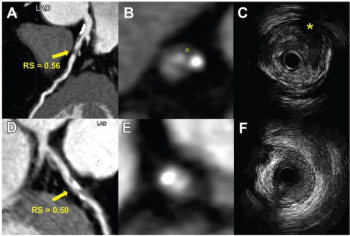

Recently published research revealed that coronary computed tomography angiography (CCTA) exams performed with dual-source CT were completed 22 minutes faster and had a nearly 28 percent higher frequency of good or excellent image quality in comparison to CCTA exams performed with single-source CT devices.